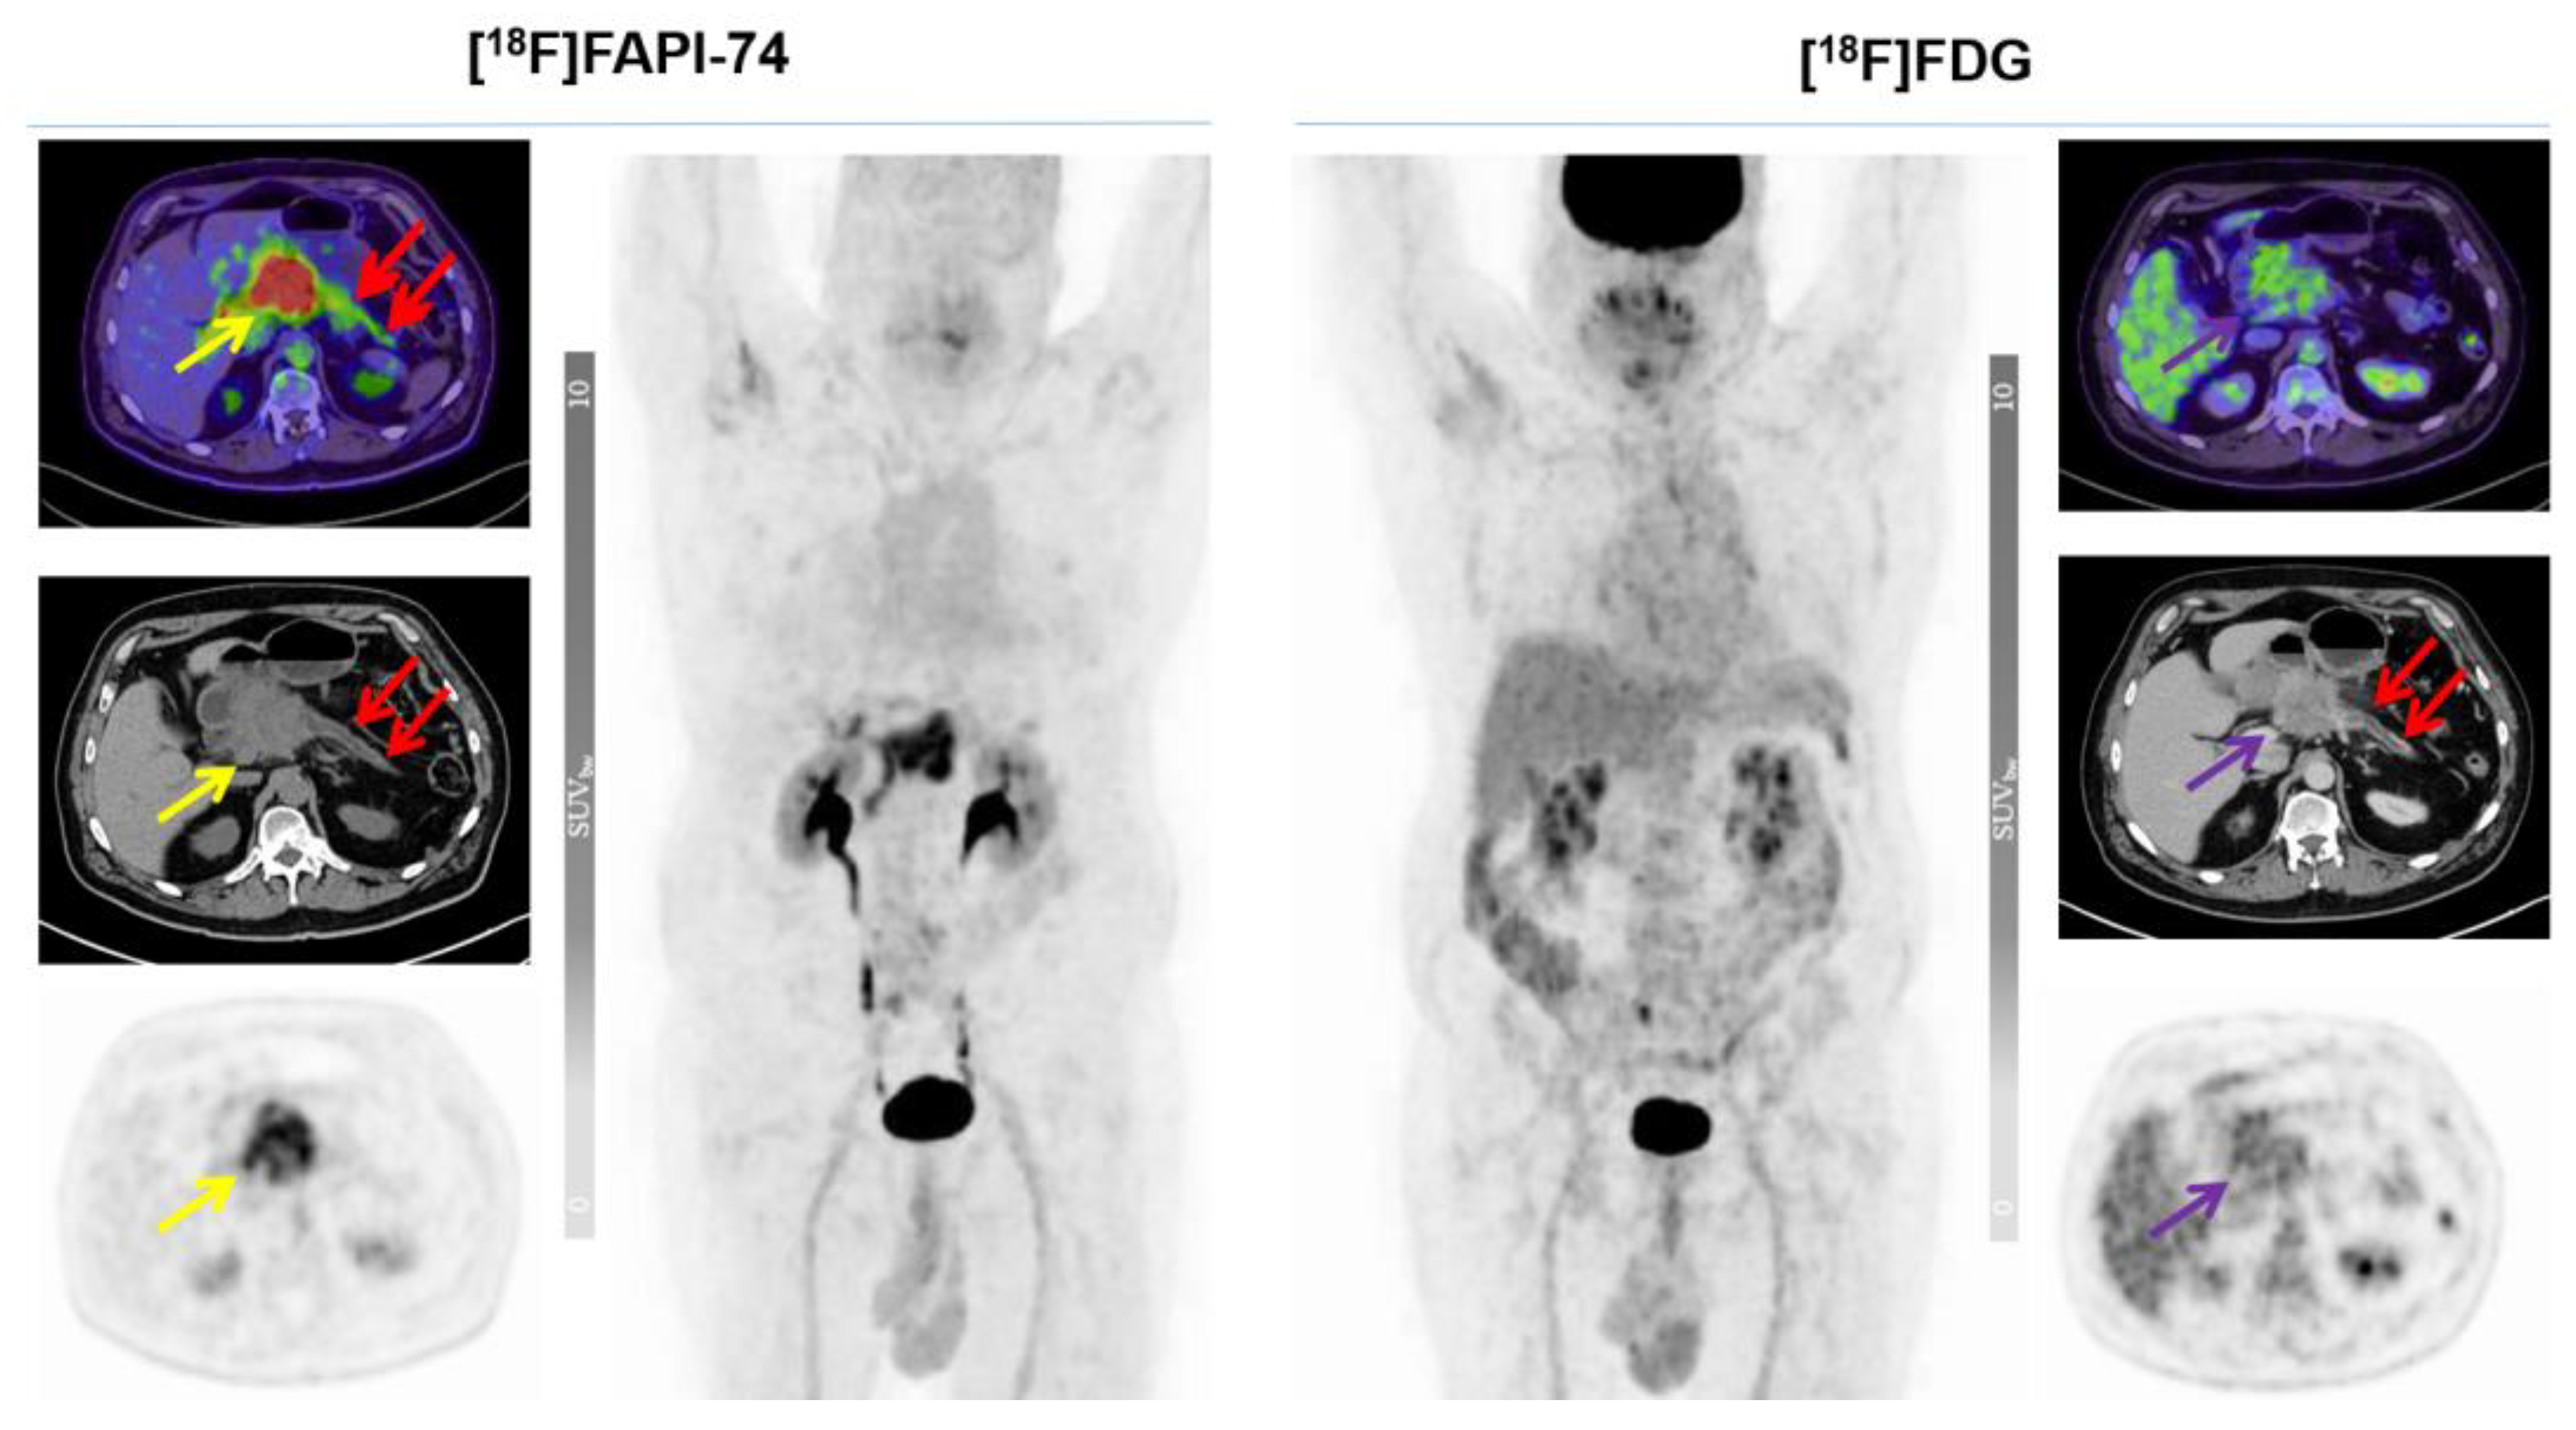

3.3. [18F]FAPI-74 Uptake in Tumor Lesions